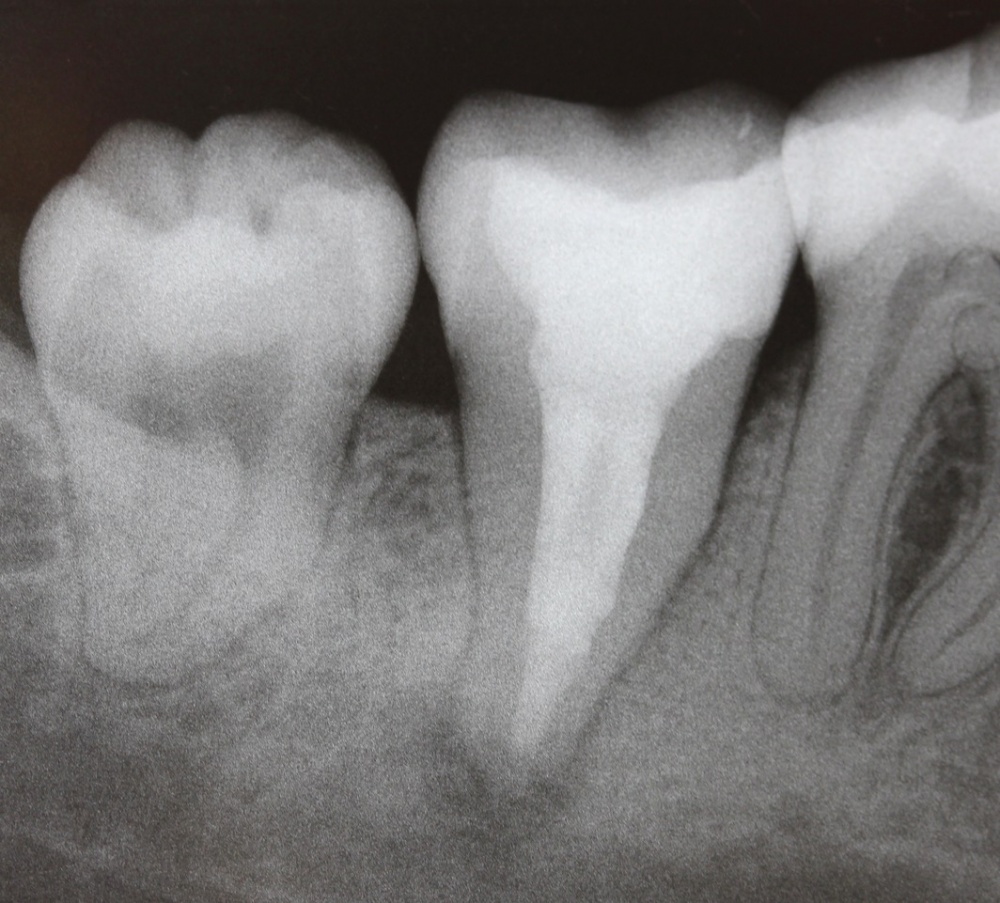

Im nächsten Fall stellte sich ein Patient mit reizunabhängigen Beschwerden und Perkussionsempflindlichkeit an Zahn 17 vor. Begleitend lag eine Lockerung Grad I bis II vor. Das daraufhin angefertigte Röntgenbild (Abb. 5) zeigt eine insuffiziente Wurzelfüllung, nebst Wurzelstift und einer umfangreichen apikalen Osteolyse. Darüber hinaus scheint Zahn 16 ebenfalls apikal beherdet zu sein und im Bereich der mesialen Wurzel besteht der Verdacht eines frakturierten Wurzelkanalinstrumentes.